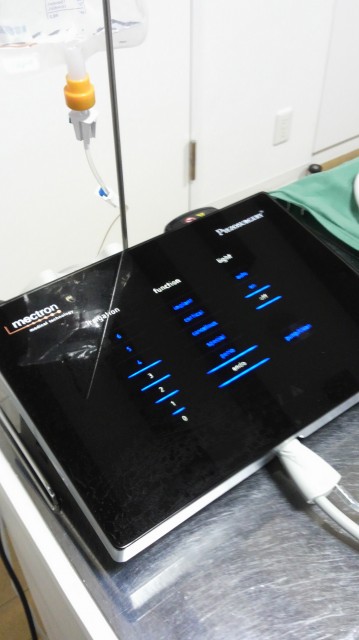

ピエゾ。

超音波振動で、硬い物は削れても、柔らかい物は切れない手術器具。

新型はブラックフェイスでかっこいい!

タッチパネル式です。